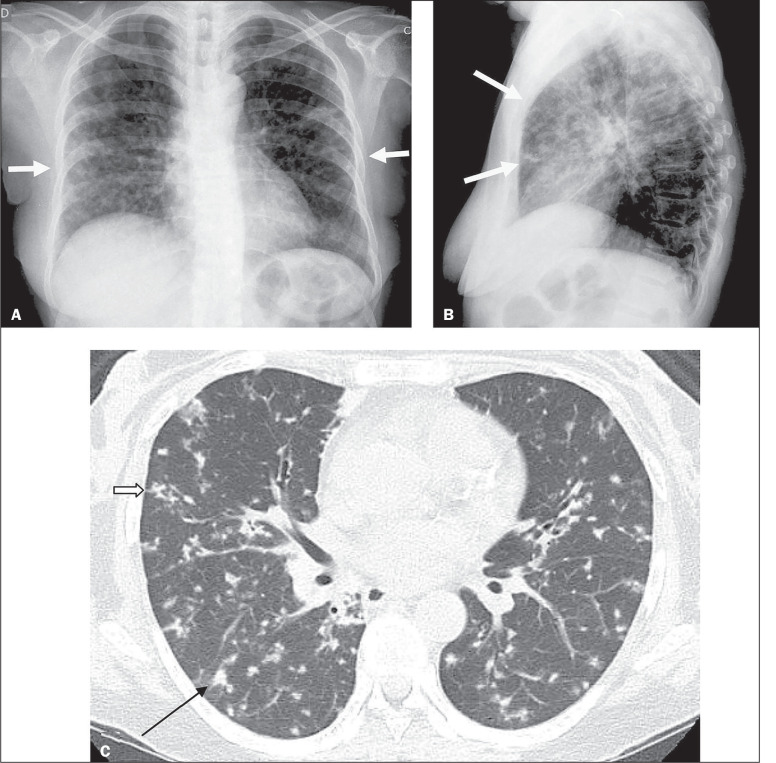

Although kidney transplantation is the best therapeutic option for patients with chronic kidney disease, the immunosuppression required greatly increases susceptibility to infections that are responsible for high post-transplant mortality. Pulmonary tuberculosis (TB) represents a major cause of such infections, and its early diagnosis is therefore quite important. In view of that, we researched the manifestations of active pulmonary TB in kidney transplant recipients, through chest X-ray and computed tomography (CT), as well as determining the number of cases of active pulmonary TB occurring over a 3.5-year period at our institution. We identified four cases of active pulmonary TB in kidney transplant recipients. The CT scans provided information complementary to the chest X-ray findings in all four of those cases. We compared our CT findings with those reported in the literature. We analyzed our experience in conjunction with an extensive review of the literature that was nevertheless limited because few studies have been carried out in lowand middle-income countries, where the incidence of TB is higher.